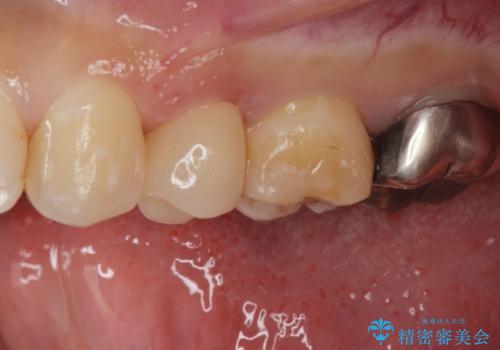

- 他院で被せた保険の白い被せ物(樹脂)をセラミックの被せ物に変えたいとの事で来院。

被せ物を外し、虫歯がないことを確認してセラミックの被せ物(ジルコニアクラウン)の治療を行いました。

白くて適合の良い被せ物が入りました。

セラミックは劣化することがなく虫歯の再発のリスクが低くなります。